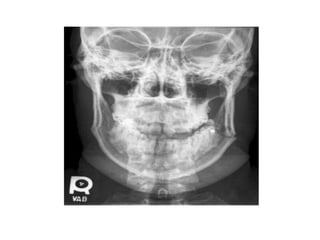

STATION 6 • APATIENT IS BROUGHT TO THE DENTAL CLINIC AFTER HISTORY OF TRAUMA DUE ROAD TRAFFIC ACCIDENT(RTA) ……UPON ORDERING FOR P/A X-RAY YOU DISCOVER THIS……

ANSWER THE FOLLOWING a)DEFINE MANDIBULAR FRACTURE b) WHAT IS THE COMMON SITE OF MANDIBULAR FRACTURES c) WHAT ARE CLINICAL FEATURES OF MANDIBULAR FRACTURES? d) WHAT ARE THE MANAGEMENT PRINCIPLES OF MANDIBULAR FRACTURES